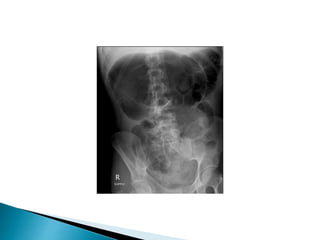

 20 yearold woman presented to the ED with 12 hours of abdominal pain, nausea. and vomiting low grade fever.  No past surgical history  PMH: Polycystic ovarian disease

• 50.

Dilated cecum

Cecum

Contrast

In Descending colon

Barium Enema

Point of Obstruction

Ascending colon